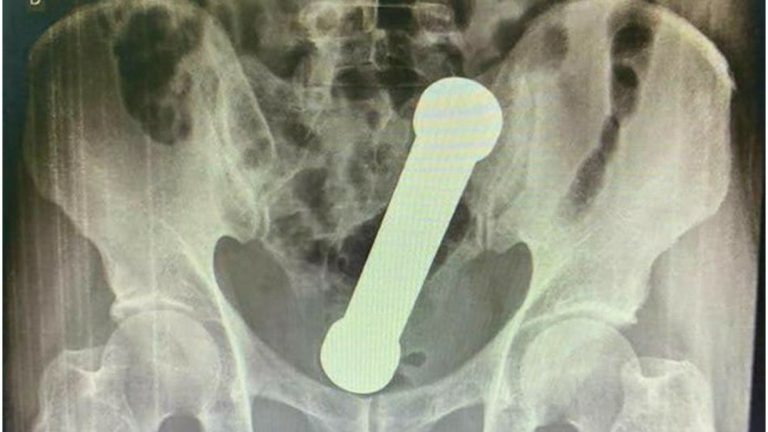

¡Insólito caso! Encuentran una mancuerna de dos kilos en el recto de un hombre